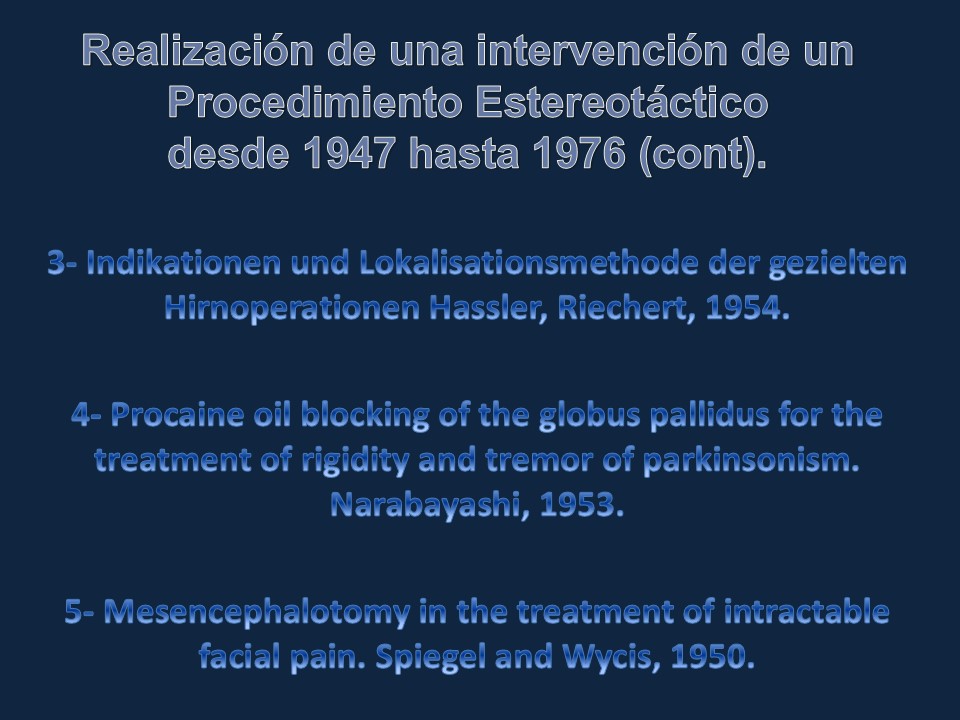

Metodología Estereotáctica o Estereotaxia

Dr. Guillermo Larrarte